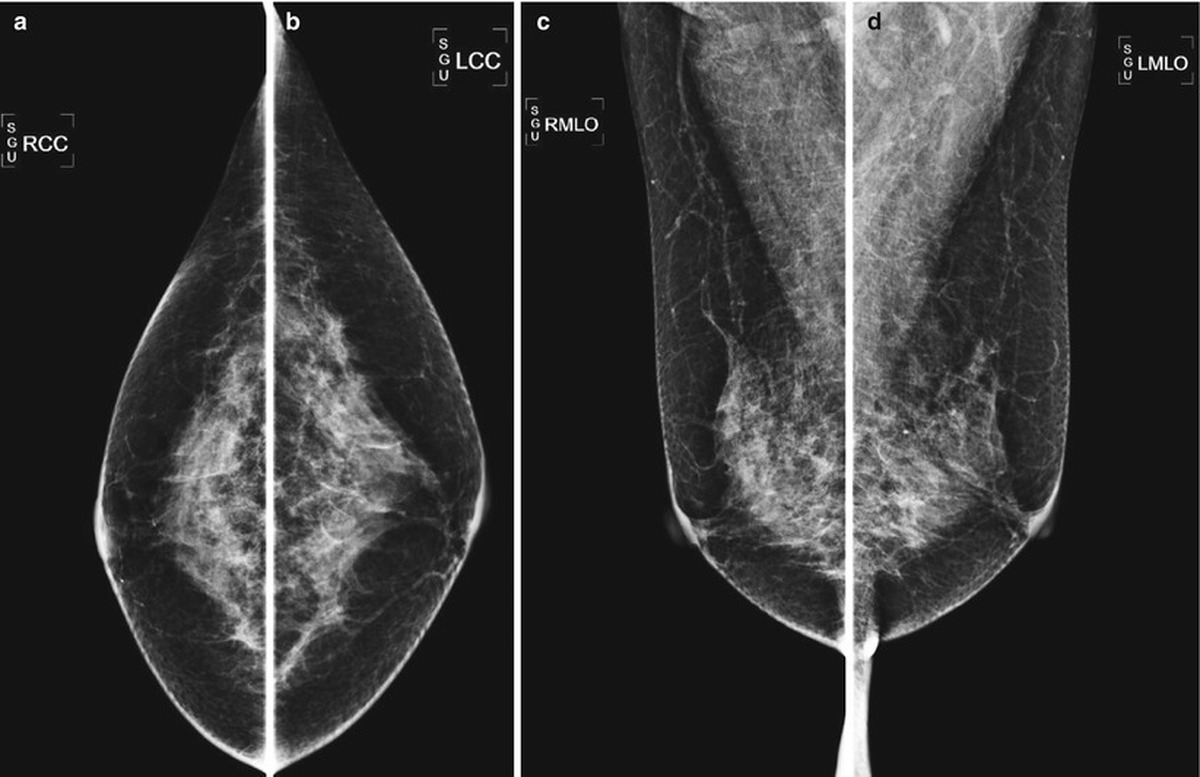

“In this project, artificial intelligence algorithms, machine learning (ML) and deep learning (DL), were used in a way that they are able to interpret mammography results,” said Parastou Kordestani Moqaddam, an assistant professor at Lorestan University of Medical Sciences.

Noting that this can increase the sensitivity necessary to improve the accuracy in interpreting the results of medical diagnostic tests, she said, “Previous studies have concluded that deep learning and machine learning can be very useful in advancing the identification of abnormalities in mammography and provide significant assistance to medical staff.”

“In this project, after reviewing the studies conducted and examining the strengths and weaknesses of these studies, the research team designed an optimal artificial intelligence assistant method for interpreting mammography images to detect abnormalities. This artificial intelligence-based tool will save radiologists' time and help young and inexperienced radiologists achieve more accurate, faster, and more reliable diagnoses,” Kordestani Moqaddam said.

“3D digital mammography, using X-ray-based imaging technology and advanced data analysis, enables the identification of small cancerous masses and the detection of lesions hidden in dense tissues. This technology is a big breakthrough, specially for women with dense breast tissue, where detection is more difficult,” said Amir Askari Raad, the managing director of Payamed Electronic company.